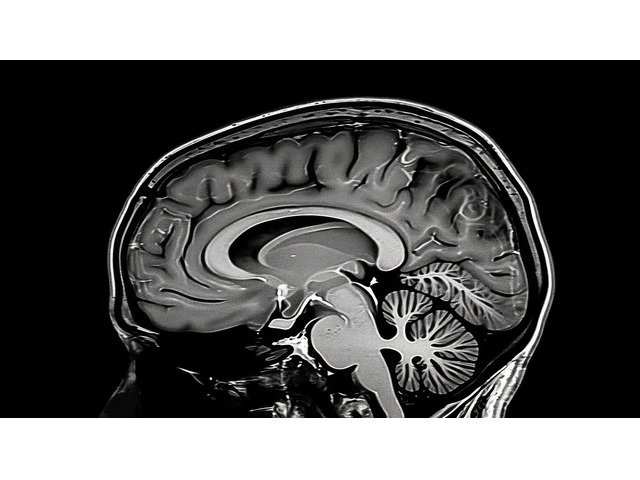

MRI test price depends on multiple factors such as the body part being scanned, thetype of MRI (contrast or non-contrast), and the diagnostic center you choose.In India, MRI scans are widely available with modern technology ensuring accurate results, and prices may vary based on location and facilities.

Body Part Matters: Brain, spine, knee, or full-body MRI scans have different pricing.

Technology Used: Advanced machines (like 3 Tesla MRI) may cost more.